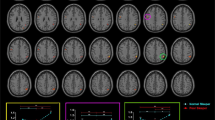

Group differences in GM volume

Compared to HO, MCI patients showed a significant reduction of the right hippocampus (PFWE-corrected = 0.002; MNI coordinates of the peak voxel: [33–11–15]), left middle temporal gyrus (PFWE-corrected = 0.001; [−45–36 5]) and right inferior frontal gyrus (PFWE-corrected = 0.001; [32 23 27]).

Serial relationship between HCY, TAC, sleep, and cerebral GM

Regression analyses revealed a positive correlation in MCI between TAC and GM in the left middle temporal lobe (PFWE-corrected = 0.002; MNI coordinates of the peak voxel: [−60–57 9]). These results are illustrated in Fig. 3A. Interestingly, GM loss in this region was further associated with increased HCY levels in MCI (PFWE-corrected = 0.014; [−53–54 6]). Group comparison of regression coefficients did not achieve statistical significance. The scatter plots of both analyses are shown in Fig. 3B and C.

Correlations between HCY/TAC levels and cerebral GM. (A) Significant results derived from a linear regression between TAC and GM (p < 0.05; FWE corrected) in MCI. Scatter plots of TAC (B) or HCY (C) against GM for HO (in blue) and MCI (in orange). The variables included in the scatter plots correspond to the standardized residuals from a simple regression with age as independent variable. The coefficients of determination (R2) and probability (p value) for each group are also indicated.

Given that GM loss in the left middle temporal lobe was significantly correlated with both increased HCY and decreased TAC levels, we tested the serial multiple-mediation effect illustrated in Fig. 1C. Results derived from this model showed that joint effects and the three-path indirect effect reached statistical significance for both total sleep time and sleep efficiency, but only in MCI. Reversing the direction of the mediation (HCY → TAC → sleep → GM loss) and of the dependent and independent variables (GM loss → sleep → TAC → HCY) yielded non-significant results.